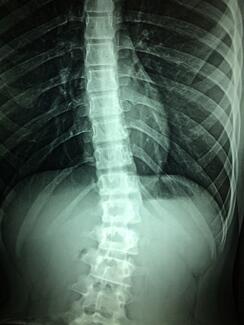

spinal xray

Conference Coverage

02/18/2022

A new study demonstrates that patients with psoriatic arthritis, as in other inflammatory diseases, are at higher risk of fractures in the vertebrae.